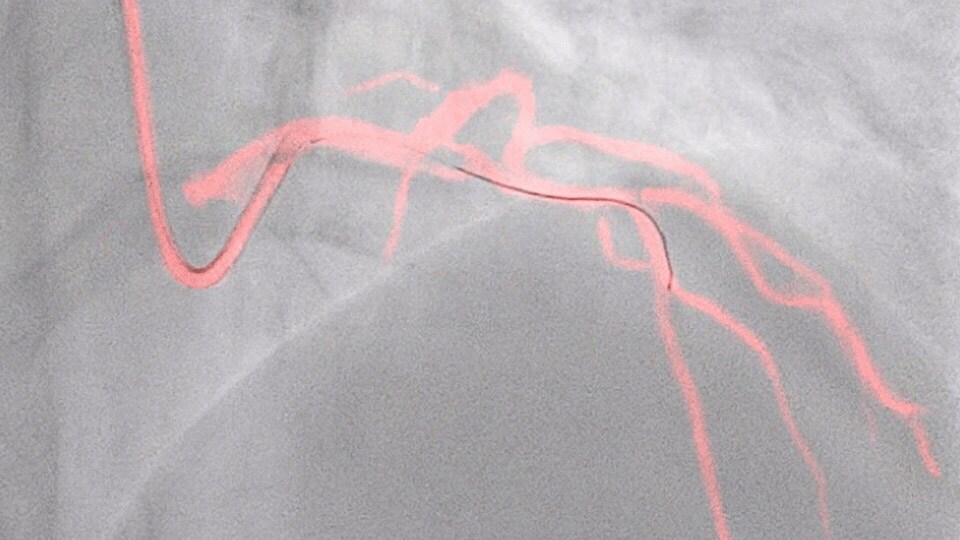

This Philips-exclusive technology provides a real-time view of the coronary arteries and removes the need for additional contrast injections.

New invasive imaging techniques and co-registration software allows PCI to be performed with limited amounts of contrast, even with zero-contrast use, to reduce the risk of CI-AKI for all patients, and especially those with renal insufficiency.

Philips PCI guidance solutions incorporate non-invasive and adjunctive IVUS and iFR modalities, requiring less contrast for proper diagnosis.